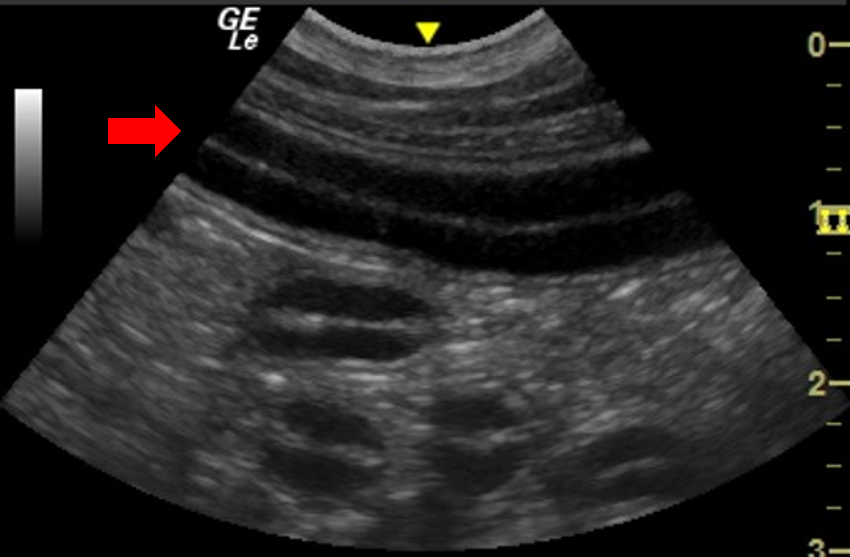

The canine duodenum is located running in a cranio-caudal direction along the right lateral body wall, following a superficial and more linear path than the jejunum (Figure 5). In contrast, the feline duodenum lies more ventrally, towards the midline. In both species the duodenum can be differentiated from jejunum by anatomical location and slightly wider wall thickness. 4,5

Figure 5. Duodenum – In this sagittal plane image of the right dorsal abdomen of a dog, the duodenum (arrow) an be visualised in longitudinal section. Deep to the duodenum, multiple loops of jejunum in transverse section can be seen.